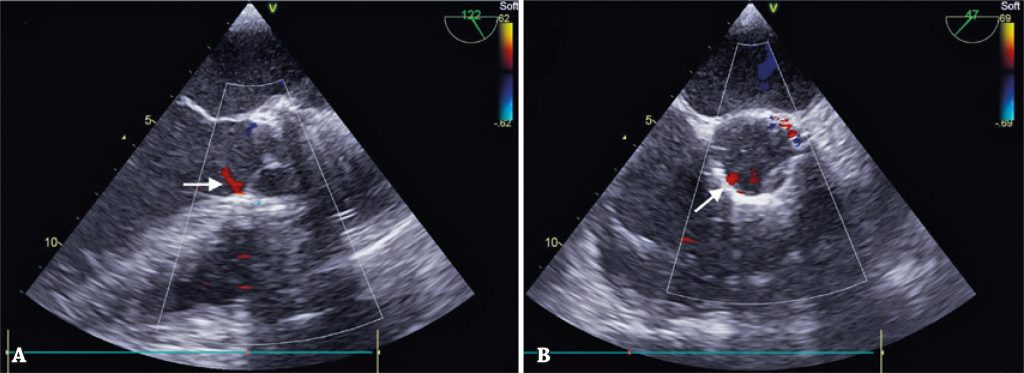

Figura 4

Resultado ecocardiográfico. Seta indicando discreta regurgitação paraprotética. (A) Eixo longo da aorta. (B) Eixo transversal da aorta.